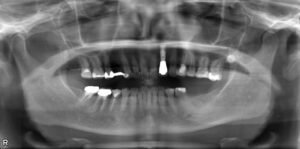

下顎大臼歯1本欠損症例

BEFORE AFTER 26歳男性/下顎1本欠損/インプラント埋込手術 【治療内容】 左下第一大臼歯が歯根のまわりで炎…